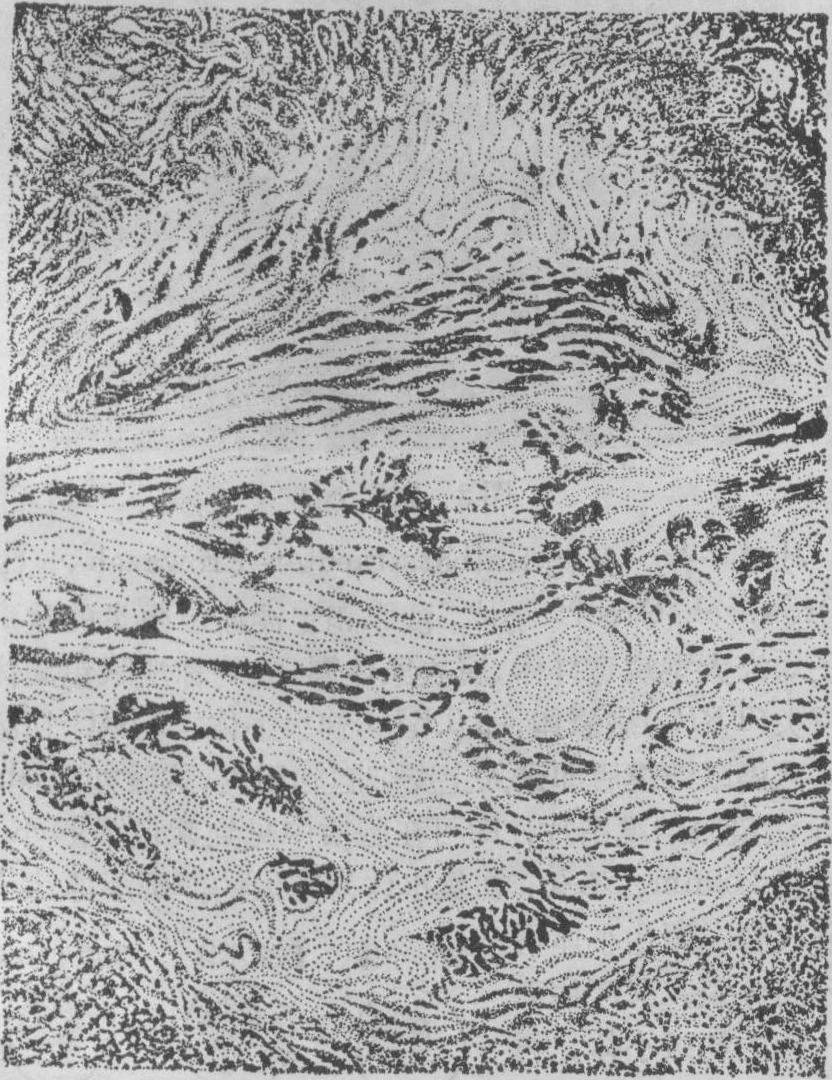

含铁小结 多见于高度淤血的巨脾中,为黄色或褐色的米粒大硬结,分散于红髓内。镜下见小结多为长条形或圆形,常在脾小梁附近。小结内有密集的纤维组织,苏木素伊红染色时常见三种不同颜色的物质: 在小结内有多数染成紫蓝色长短不一的纤维条,条间夹杂有灰绿色半透明杆状结晶样物质,外层有多量褐黄色的含铁血黄素颗粒。从前曾把这些杆条状物质当作真菌,误认是本病的病原体,其后证实它只是铁和钙盐沉积的胶原纤维。凡是能引起脾静脉淤血的病,如门脉性肝硬化、晚期血吸虫病等都能形成这种结节。可能是因为脾淤血时,有的小静脉因内压过大而发生小出血,出血后红细胞破坏,血红蛋白分解,形成含铁血黄素,同时出血机化,纤维组织增生,终于形成这样的小结。故此小结实为脾髓内陈旧小出血的遗迹。含铁小结还见于镰形红细胞性贫血,因镰形红细胞较易阻塞脾的小血管,引起局部组织缺血坏死,以后发生纤维化和钙化,同时坏死的红细胞分解形成铁质,在局部沉积而成。

图2 脾的含铁小结